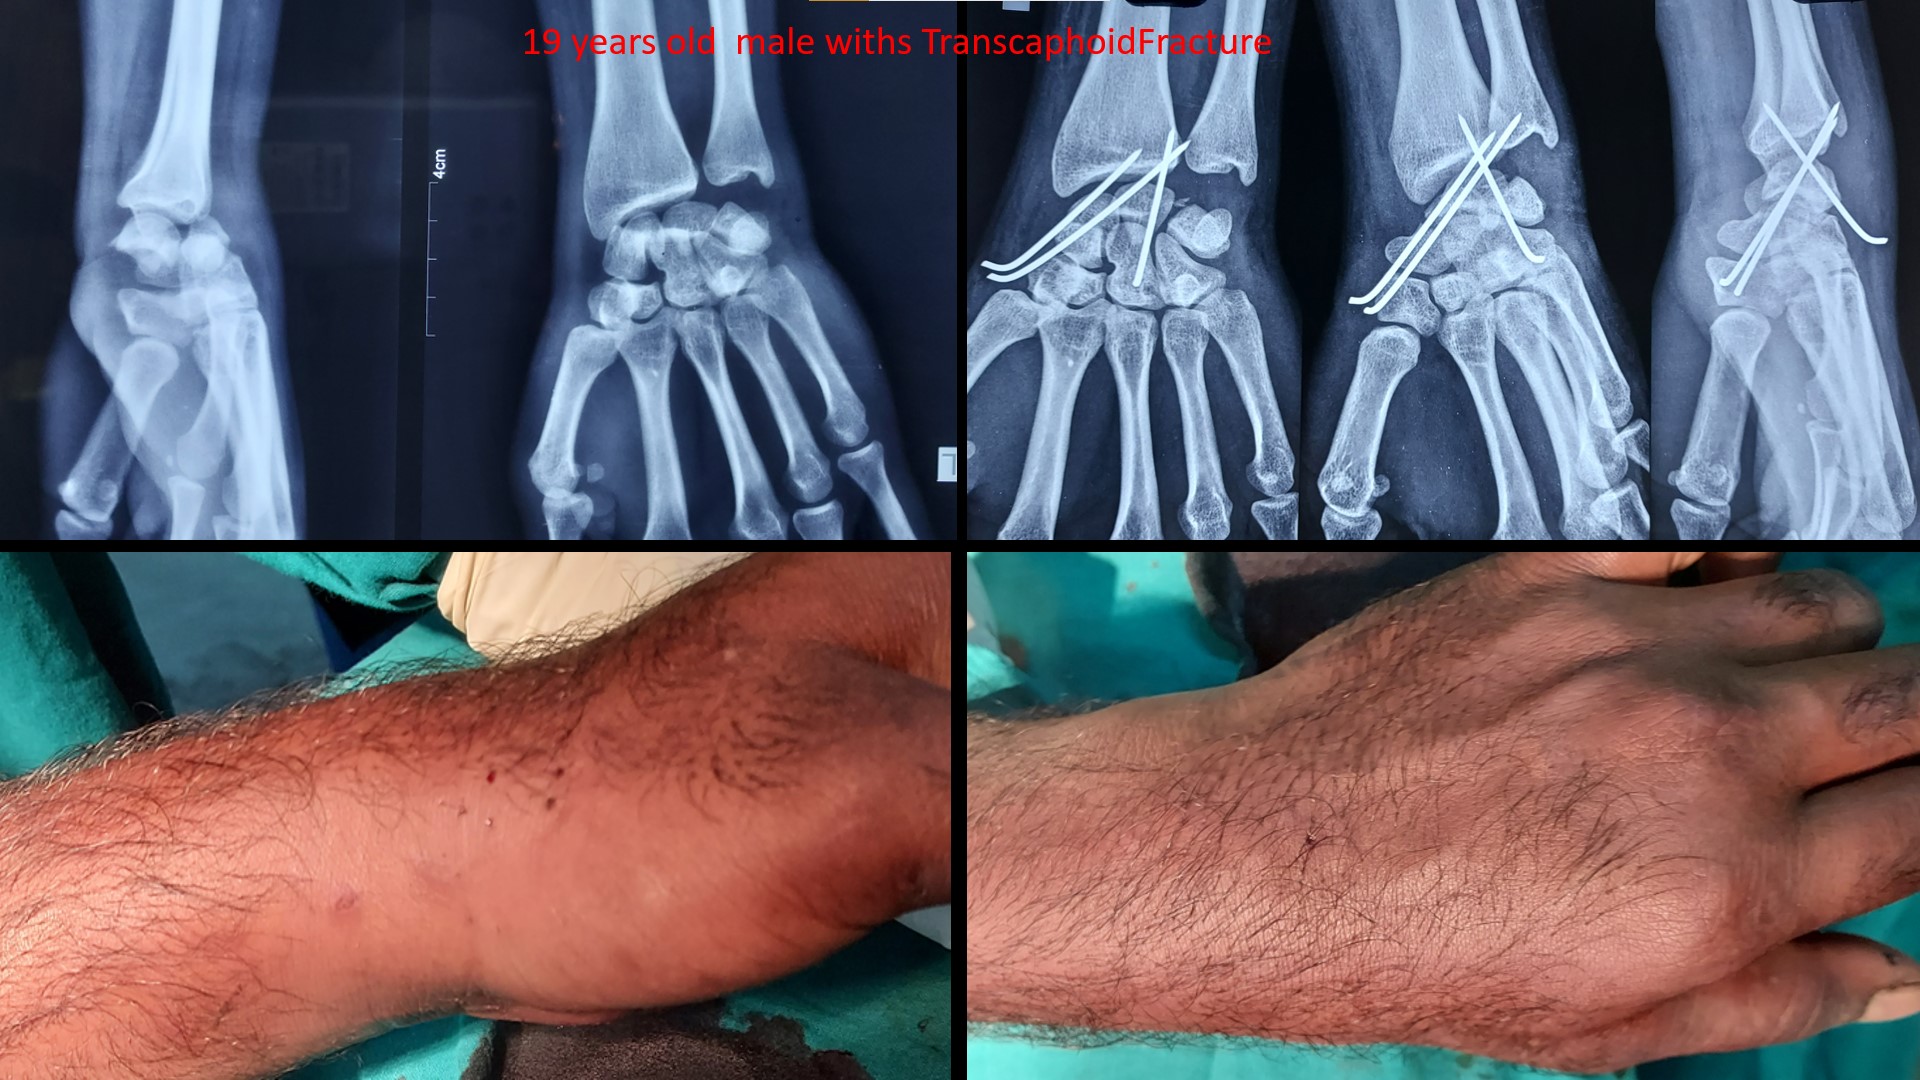

Fracture Scaphoid